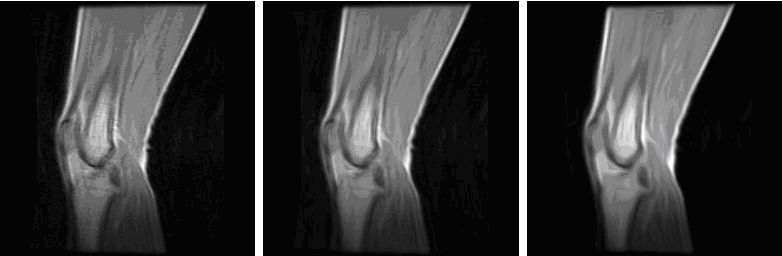

Figure 1 shows the results of applying the coherence-enhancing anisotropic diffusion filter to an example MR knee image.

Figure 1. Example of coherence-enhancing diffusion